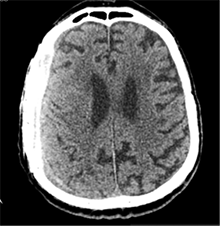

Praėjus dar 2 sav., pacientas iš slaugos ligoninės atvežtas dėl vangumo, dezorientacijos, nerišlios ir sulėtėjusios kalbos. Atlikus GKT, dešinėje pusėje po kraniotomijos lopu įtarta poūmė (ūmi) epidurinė hematoma, nesant VSD. Per parą pacientas operuotas. Operacijos metu po minkštaisiais audiniais rasta kraujo sankaupa su seroziniu komponentu, paimtas bakteriologinis pasėlis. Po KPL rasta krešulių su skystu krauju ir seroziniu komponentu. Paimtas antras bakteriologinis pasėlis, įtariant infekciją. Hematoma (seroma) pašalinta. Žaizda plauta mažos koncentracijos betadinu ir fiziologiniu tirpalu. Kraujavimo iš KSD nepastebėta. Nuspręsta KPL grąžinti – labiau tikėtina epidurinės seromos (EDS) diagnozė. Siekta uždaryti „negyvąjį“ epidurinį tarpą, pakabinant KSD centre prie KPL siūlais, tačiau KSD buvo nepaslankus, tampriai priaugęs prie smegenų. Atlikus kontrolinę GKT (9 pav.), nustatyta teigiamų pooperacinių pakitimų, smarkiai sustorėjęs KSD, tarpas tarp KPL ir KSD. VSD nenustatyta. Po operacijos paciento bendroji būklė buvo stabili. Reakcija buvo kiek sulėtėjusi, tačiau vyras gebėjo atsakyti į elementarius klausimus. Teigiama klinikinė dinamika. Po savaitės pacientas tapo labai vangus, sulėtėjo, skundėsi silpnumu, kalbėjo nesklandžiai. Pakartojus GKT (10 pav.), nustatyta padidėjusi epidurinė skysčio sankaupa, panaši į mišraus tankio hematomą (apie 64 ml tūrio) dešinėje pusėje frontotemporoparietaliai, padidėjusi VSD į kairę – iki 4 mm. Kadangi pacientas per tą patį randą jau operuotas 6 kartus, o po operacijų pastebimos vis atsinaujinančios pakartotinės EDS, priimtas sprendimas neskirti operacinio gydymo. KPL turėjo daugybinių perforacijų, todėl nuspręsta atlikti subgalinio tarpo punkciją, tikintis, kad per perforacijas išbėgs EDS. Atlikus punkciją, gauta 20 ml serohemoraginio skysčio. Po procedūros paciento būklė pagerėjo, jis tapo kiek aktyvesnis, tačiau efektas nebuvo patenkinamas. Kitą dieną nuspręsta punktuoti pakartotinai, gauta 4 ml serohemoraginio skysčio. Tūris buvo nepakankamas teigiamam efektui gauti. Priimtas sprendimas skirti lašinių infuzijų ir švelnią osmoterapiją neurologinei simptomatikai sumažinti. Punkcijos nedavė norimo efekto, todėl nuspręsta suformuoti poodinę neigiamo slėgio drenažinę sistemą po minkštųjų audinių lopu. Į subgalinį tarpą įvestas 20G periferinės venos kateteris, fiksuotas prie odos ir sujungtas su uždara vakuumine sistema, tikintis nuolatinio drenavimosi smegenų kompresijai sumažinti. Per 5 lovadienius išsiskyrė apie 50 ml serohemoraginio skysčio. Atlikus kontrolinę GKT, buvo matyti teigiama dinamika (11 pav.). Dėl infekcijos profilaktikos vakuuminė sistema pakeista 2 kartus. Įvedus vakuuminę sistemą, po 12 lovadienių paciento būklė pagerėjo, jis tapo aktyvesnis, į klausimus atsakydavo prasmingai, paliepimus vykdydavo visomis galūnėmis. Vakuuminė sistema pašalinta. Po 2 dienų atlikta GKT (12 pav.). EDS dešinėje pusėje regresavo, smegenų kompresijos nenustatyta. Esant stabiliai būklei ir teigiamai dinamikai, pacientas grąžintas į slaugos ligoninę.

10 pav. Bėgant laikui, padidėjusi EDS (dešinėje F-T-P, padidėjusi VSD į kairę iki 4 mm)